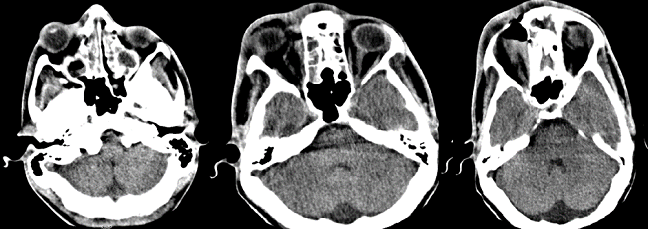

El estudio informó ausencia de línea de fractura; todas las cavidades que conforman los senos paranasales, exceptuando seno esfenoidal, se encontraban prácticamente ocupadas por material hiperdenso de aspecto inflamatorio, con formación de nivel en seno maxilar derecho y varios niveles en senos frontales, evidencias relacionadas con pansinusopatía. Se visualizó, además, proptosis del globo ocular de este lado, con aumento de la grasa alrededor del párpado y de la órbita, acompañado de colección con nivel hidroaéreo en la cara interna de la órbita, a nivel de los tejidos blandos subperiósticos, con erosión de la pared de las celdillas etmoidales contiguas y pared posterolateral derecha del seno frontal, presencia de gas periorbitario y perinasal anterior, con el aspecto de celulitis preseptal y orbitaria con absceso subperióstico y enfisema subcutáneo. A nivel de fosa posterior, fue visible un ensanchamiento del espacio subaracnoideo, con un IV ventrículo normal, por la presencia de una megacisterna magna (Fig. 1 y Fig. 2). En cortes a nivel de la región supratentorial se evidenció ligero borramiento de surcos y circunvoluciones por signos de hipertensión endocraneana (HTE). En la porción anterosuperior de la región frontal derecha se observó, además, imagen hiperdensa, de márgenes bien definidos, convexa hacia el parénquima cerebral, con grosor máximo de 23 mm, sin edema perilesional, la cual provocaba efecto de masa con compresión del asta frontal del sistema ventricular ipsilateral y desplazamiento 9 mm de estructuras de la línea media, por colección epidural (Fig. 3).

Todos estos hallazgos tomográficos condujeron a la siguiente impresión diagnóstica: Colección epidural, signos de HTE, celulitis orbitaria y absceso subperióstico secundarios a pansinusopatía complicada; megacisterna magna. El paciente fue intervenido quirúrgicamente, con evolución clínica favorable, a pesar de la pérdida de visión del ojo afectado.